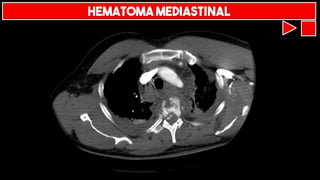

HEMATOMA MEDIASTINAL

> 8 cm

Traqueia desviada

Mediastino

alargado